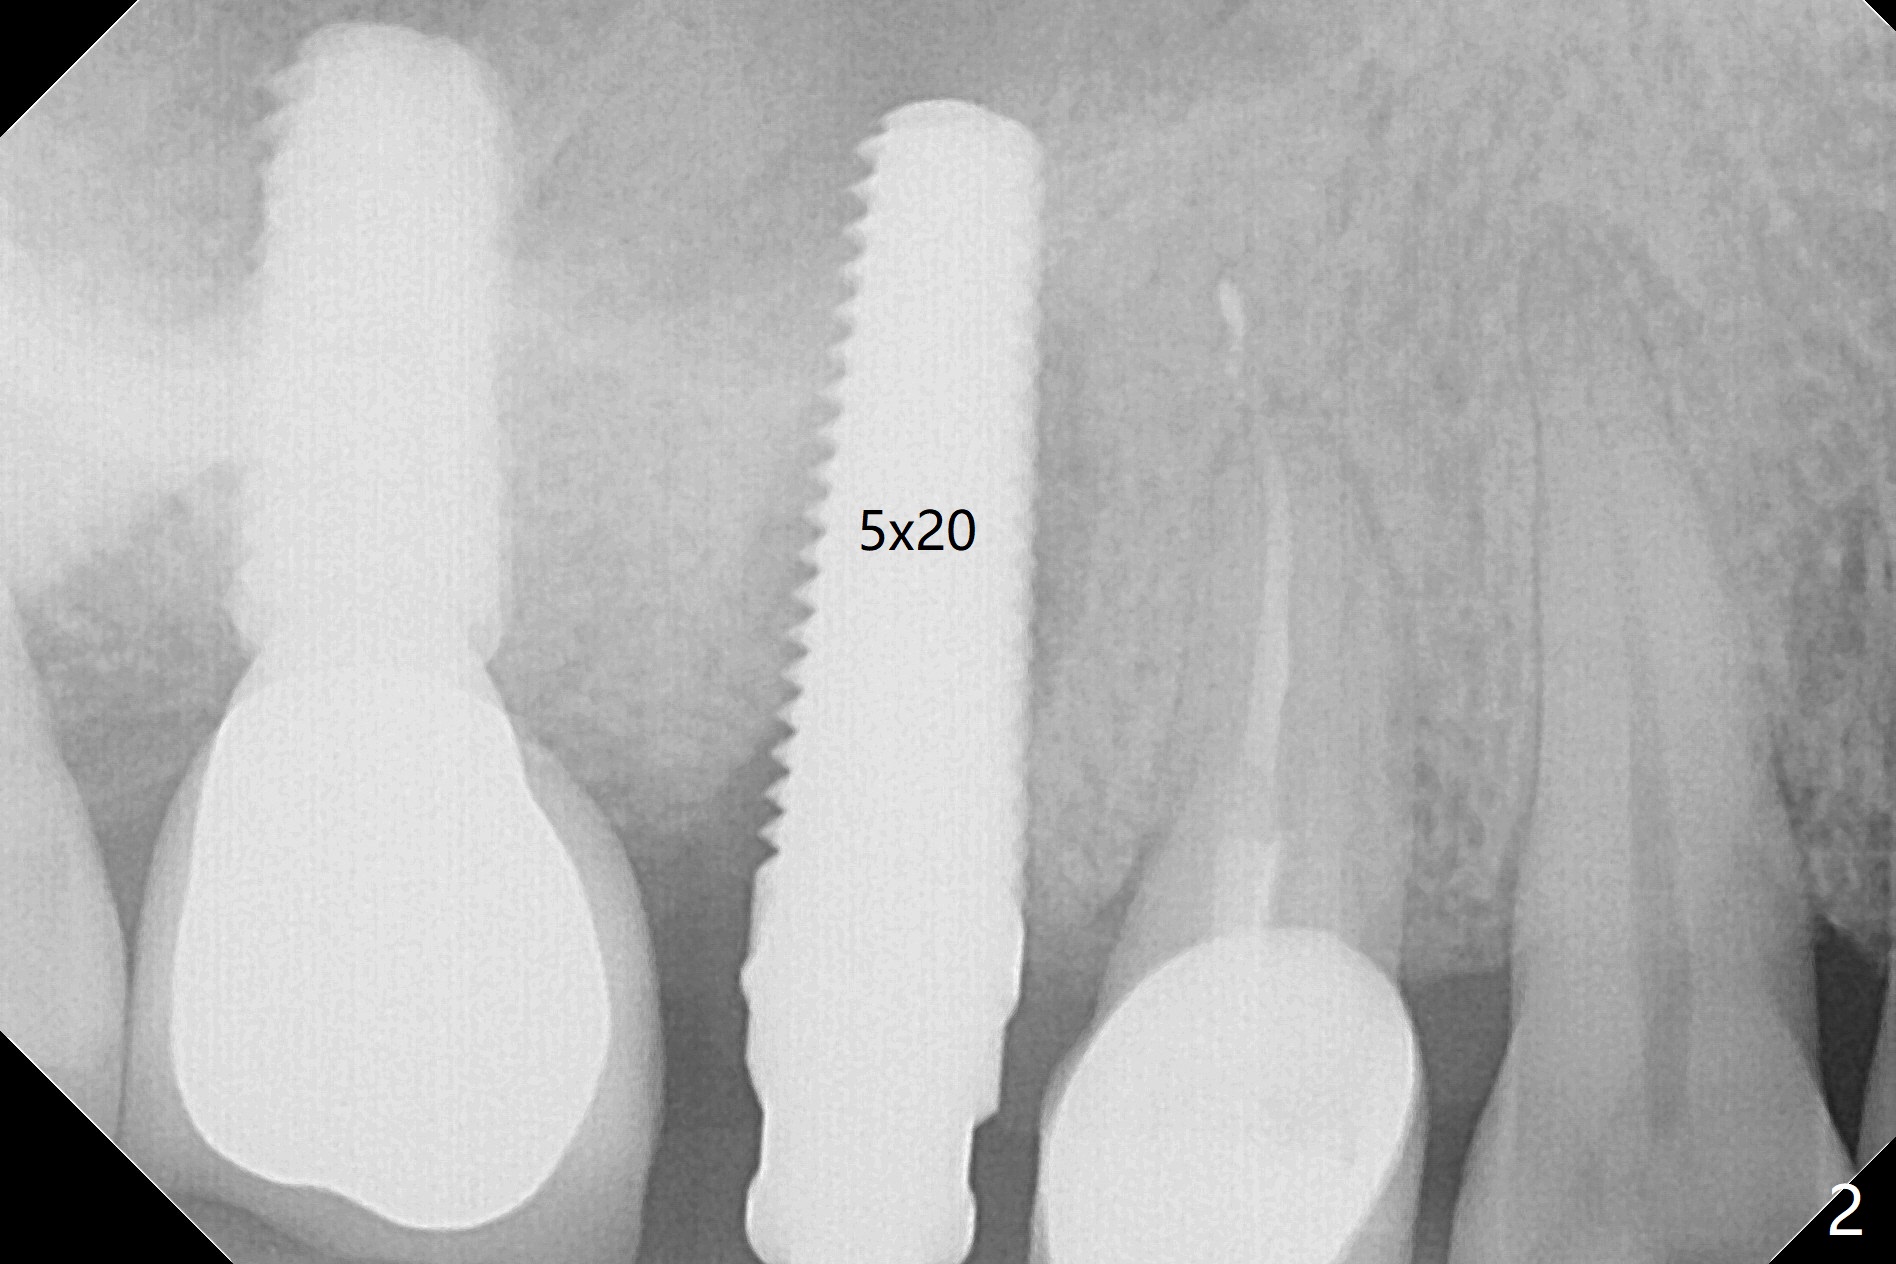

In spite of a fistula at #4, the buccal plate is present because of the exostosis (Fig.1 *). Since the socket is long and narrow, it is difficult to initiate osteotomy in the distal slope. Since the buccal plate is low, osteotomy is established as palatal as possible. The sinus floor is thin, but hard to elevate with Magic Sinus Lifter. Use of 3 mm Magic Expander leads to sinus floor break through and membrane perforation. After increase in the osteotomy with sequential expanders, a 5x20 mm tap is inserted with stability (Fig.2). Two pieces of PRF membrane are inserted for sinus membrane repair, followed by small amount of allograft (mixed with PRF, Fig.3 *) and a 4.5x17 mm dummy implant. A 5x17 mm tissue level implant is placed with >45 Ncm; with immediate placement of a 4x3 mm abutment (Fig.4), an immediate provisional is fabricated. There is no postop nasal hemorrhage. The immediate provisional has occlusal perforation 1.5 months postop. The tooth #13 has mobility due to its overuse and missing the teeth #14 and 18. Bitewing taken while redoing crown for #30 shows that the implant threads are subcrestal (Fig.5). There is no crestal bone resorption 6.5 months postop (Fig.6,7), while the periradicular radiolucency decreases (Fig.7).